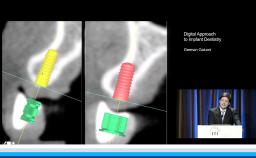

In his lecture, clinical considerations and indications for dental implants are analyzed in the context of their direct application to digital implant-prosthetic rehabilitations. Recommended planning steps and treatment procedures are presented through scientific evidence.

- assess associated technology for suitable treatment planning

- widen treatment planning options using a selective approach